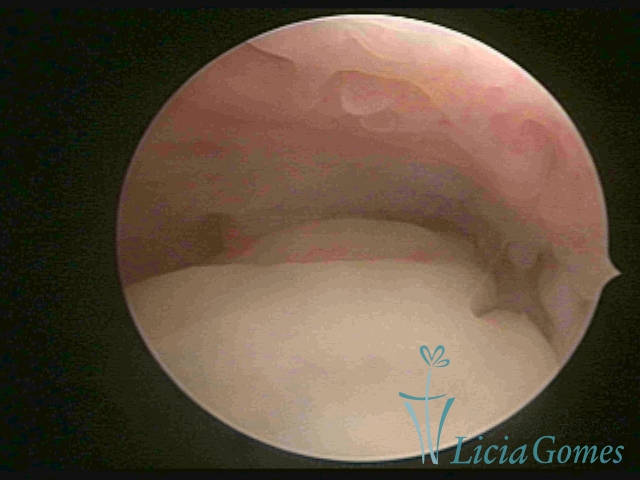

ENDOCERVICAL POLYPS

Benign tumors resulting from the reactive focal proliferation to inflammatory processes or hyperestrogenism situations, which may be sessile (with a large implantation) or stalked.